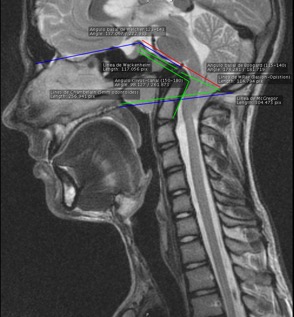

Einige Diagnosen können auch durch eine Kernspintomographie – Gehirn- oder Schädel-MRT – gestellt werden, aber wenn die Fehlbildung einmal entdeckt wurde, ist die CT für eine optimale Untersuchung indiziert.

Abb.2 Platybasie durch ein MRT gesehen.